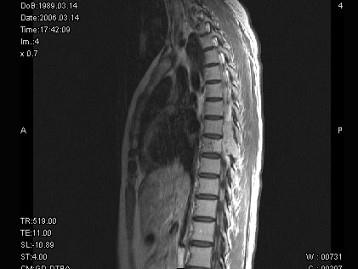

问题 女,18岁,腰以下麻木、双下肢无力,行走困难。PE:双下肢肌力IV+级,肌张力高,腱反射活跃,T以下痛觉消失,深感觉减退,请根据所提供图像,选择最可能的诊断 ( )

选项 A、脊膜瘤 B、淋巴瘤 C、骨母细胞瘤 D、骨巨细胞瘤 E、神经鞘瘤

答案 D